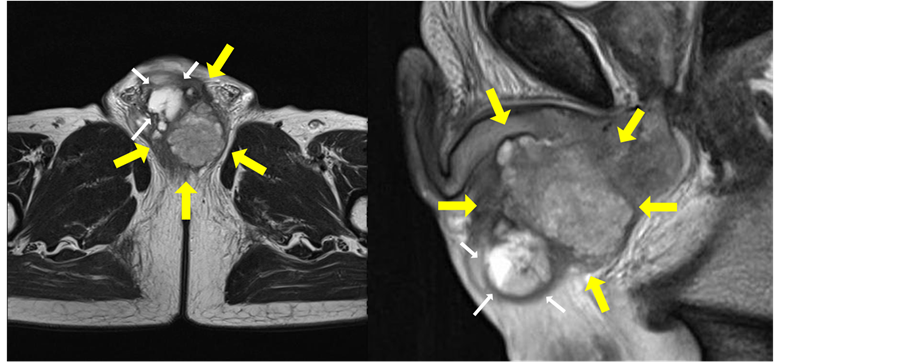

A 69-year-old man with no past medical history was referred to our hospital complaining of dysuria and gross hematuria associated with a rapidly growing perineal mass. Physical examination revealed a stiff mass in the perineum. Digital rectal examination showed no abnormal findings. Serum laboratory data showed inflammatory findings, and among several tumor markers measured, only the SCC antigen level was slightly high at 2.4 ng/mL. Magnetic resonance imaging (MRI) examination revealed a tumor (45 × 52 × 55 mm) posterior and inferior to the pendular urethra with a cystic lesion inside, which was invading the corpusspongiosum (Figure 1). Urine cytology was positive, suggesting SCC. Cystourethroscopy revealed a constriction at the posterior urethra but no clear finding of urethral tumor. The patient then developed urinary retention and for which percutaneous cystostomy was performed. Percutaneous tumor needle biopsy showed SCC. Tumor resection and total penectomy were then performed. The bilateral testes were preserved. The excised tumor appeared as a solid and grayish mass, approximately 5 cm in size, with a yellowish granulomatous lesion next to the urethra (Figure 2). Pathohistological findings revealed well-differentiated SCC arising from the paraurethral region (Figure 3(A)). Neither the scrotal skin nor the urethra was directly infiltrated by the tumor (Figure 3(B), Figure 3(C)), while the urethral constriction was involved with the granulomatous lesion which was determined to be inflammation associated with tumor spillage (Figure 3(D)). The surgical margin was negative. Postoperatively, no additional treatment was administered. As of 70 months after surgery, the SCC antigen level was normal, and the patient remained free of disease.

Figure 1. Magnetic resonance imaging revealed a tumor posterior and inferior to the pendular urethra. Large arrows indicate tumor and small arrows indicate the cystic lesion. Left panel: transverse plane. Right panel: sagittal plane.

In the present case, a cystic lesion was identified within the tumor by MRI (Figure 1), but this lesion was collapsed at the time of the percutaneous biopsy by chance. Then the cyst was shrunk and compressed by the tumor in the resected specimen. There was a granulomatous inflammatory lesion next to the urethra with tumor cell spillage (Figure 3(D)). This suggests that tumor cells were spilling into the necrotic tissue due to inflammatory change, which resulted in the positive urine cytology. Neither the urethra nor the skin, which is a common primary site of SCC among perineal organs, was directly involved.

There are several hypotheses as to the origin of SCC, including ectopic squamous cells in the paraurethral tissue, the urethral glands such as Cowper’s gland or Skene’s glands, and a paraurethral cyst as reported previously [6] . Whereas the paraurethral cystic lesion identified on MRI is considered as a possible origin in the present case (Figure 1), the histological examination could not confirm this due to the shrinkage of the cyst by the previous biopsy.